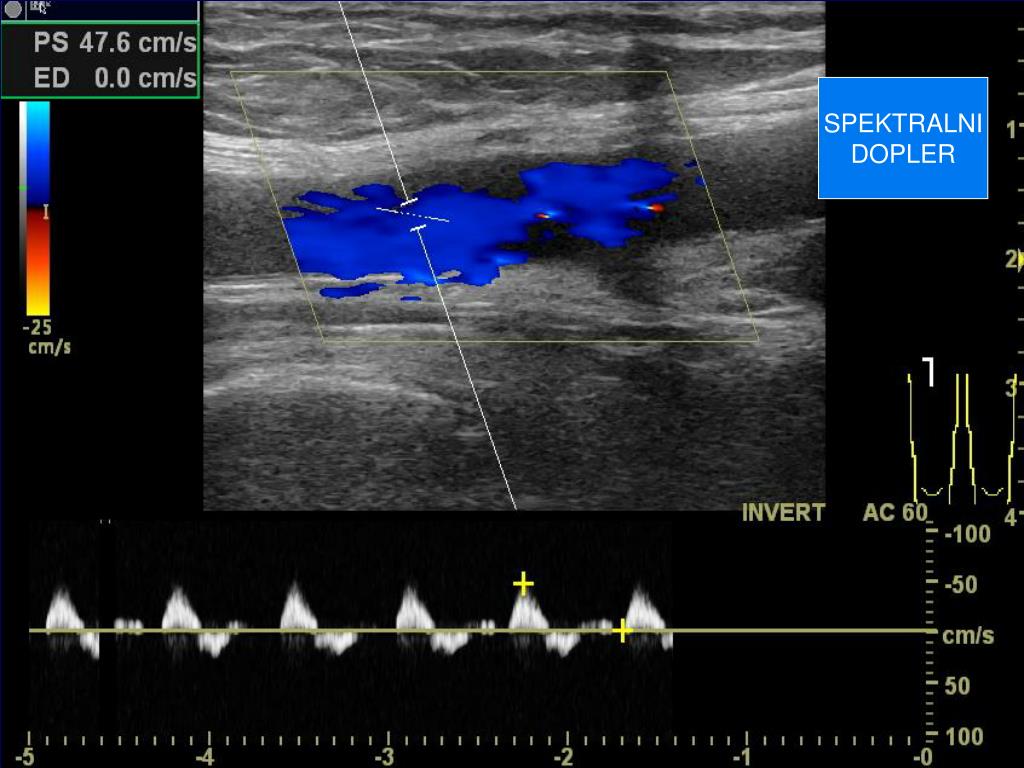

19. SPEKTRALNI DOPLER

20. SPEKTRALNI DOPLER